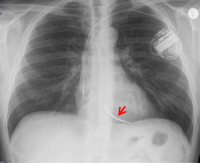

Bild 1: Zweikammer-ICD mit Elektrode im Vorhof und Defibrillations­sonde (Pfeil) in der rechten Herzkammer